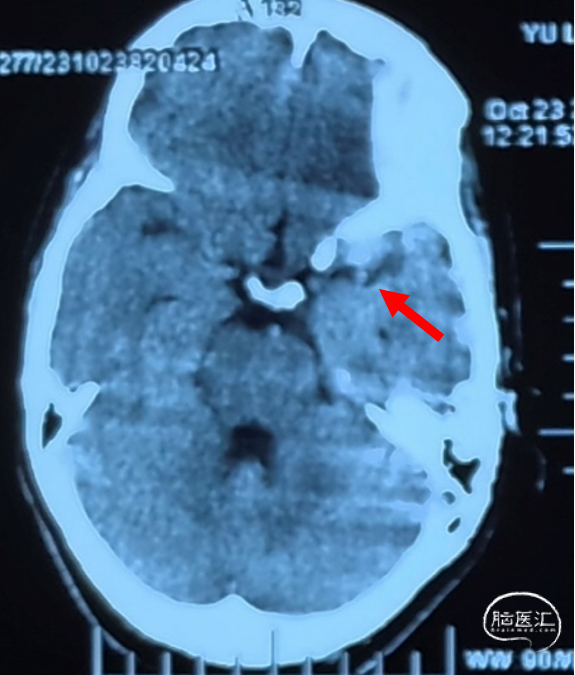

CT平扫

AN长径9.14mm

远端血管大脑中直径2.34mm、近端颈内末端4.25mm